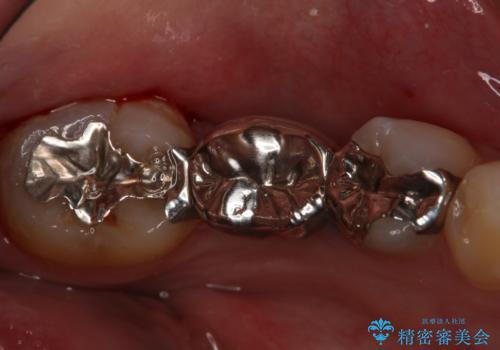

- 左下奥歯のブリッジのやり変え希望のため来院された患者様です。

支台歯部分はインレー形態でしたが強度や維持性を考慮しクラウン形態への変更を計画しました。

患者様の希望によりフルジルコニアブリッジを選択しました。